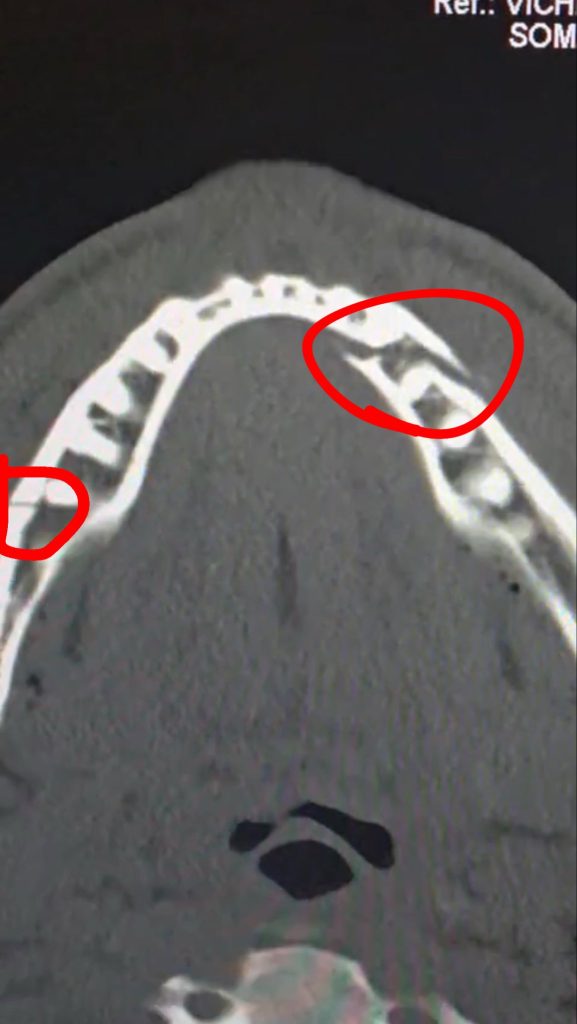

Paul confirmed the report by posting on X (formerly Twitter) that he had undergone surgery to fix the broken jaw he suffered against Joshua according to the Ring Magazine.

“Two titanium plates on each side. Some teeth removed. Everything went smooth. Thanks for all the love. Lots of pain and stiffness. Gotta eat liquids for 7 days” he wrote.